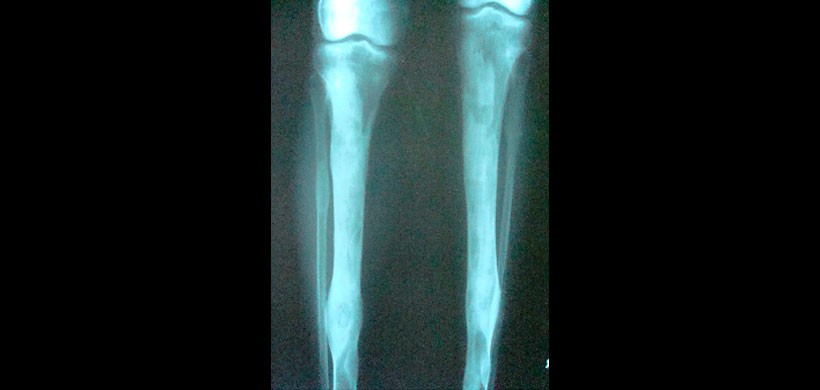

Figura 8: Vista lateral de la tibia con evidencia de esclerosis de la parte superior y media del eje de la tibia junto con áreas líticas en la irregularidad esclerótica del hueso.